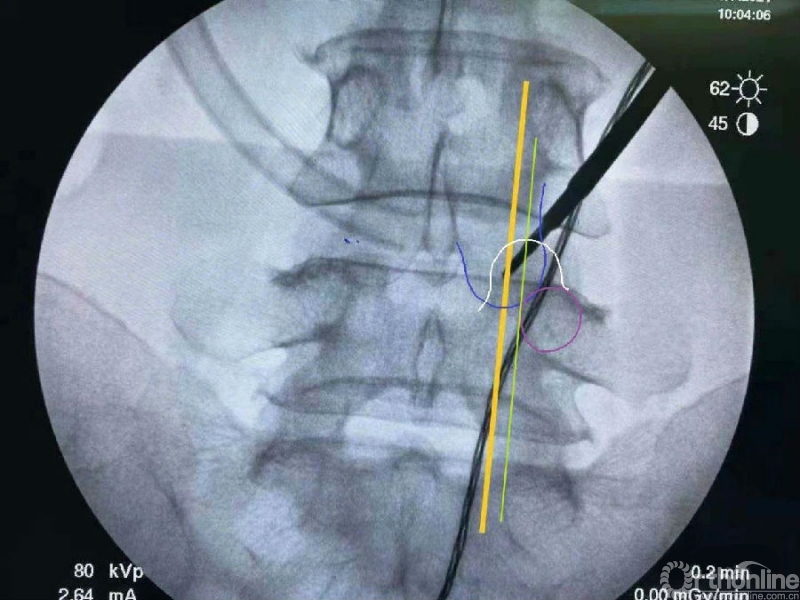

我们选用mark磨钻在下关节突上钻孔固定进行透视来确定关节突内缘磨除的外界。

定位磨钻细小,且可立于钻孔内进行透视定位。

术前克氏针确定内镜口位置位于椎板稍微偏远,是一个比较理想的定位。

内镜监视下使用mark小磨钻进行第一定位,发现定位线过于偏内。

然后在内镜监视下于第一个孔的外侧进行第二次定位。

第二次定位虽然并位于椎弓根内缘线上,但是我们觉得本病历参考内缘线的话可能会把下关节突的2/3磨掉,所以我们选择第二个接近椎弓根内缘线的定位孔作为镜下下关节突内缘切除的外界。

术中第一次及第二次的两个定位孔